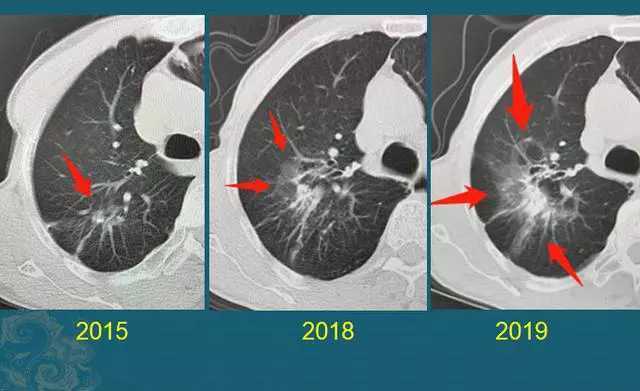

1. 恶人总会露出真面目,癌细胞会偷偷增长,而良性结节一般不变化,或者会逐渐缩小甚至完全吸收。

下图这位女士就是如此,7年前发现左肺“硬结灶”,以一种很缓慢的速度逐渐长大,去年做了手术切除:

这种肺癌相对比较温柔,如果是80多岁以上的老人,可以不急于手术,定期跟踪也可以,说不定过些年就会有更好的办法来根治。